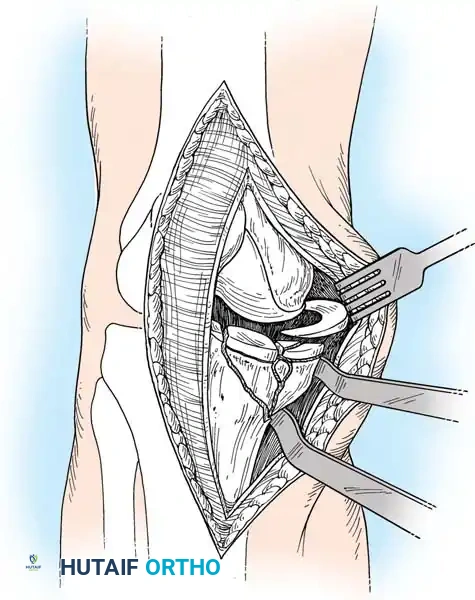

يتم اختيار الشق الجراحي بناء على موقع الكسر كما ظهر في الأشعة المقطعية.

النهج الجراحي للوصول إلى مفصل الركبة

المدخل الأمامي الجانبي يُستخدم لكسور الهضبة الخارجية، حيث يتم رفع الأنسجة بحذر للوصول إلى المفصل ورؤية الغضروف الهلالي وسطح العظم المكسور. أما المدخل الخلفي الداخلي فيُستخدم لكسور الهضبة الداخلية، ويتطلب وضعية خاصة للمريض للوصول الآمن للكسر بعيدا عن الأوعية الدموية.

أولا الرد المفصلي ورفع العظم

في حالات الكسور الانخسافية، يجب رفع السطح المفصلي ليعود لمستواه الطبيعي. يتم عمل نافذة صغيرة في العظم السليم أسفل الكسر، ويتم إدخال أداة خاصة لرفع الأجزاء المنخسفة برفق تحت الرؤية المباشرة واستخدام جهاز الأشعة داخل غرفة العمليات.

رفع سطح المفصل المكسور أثناء الجراحة